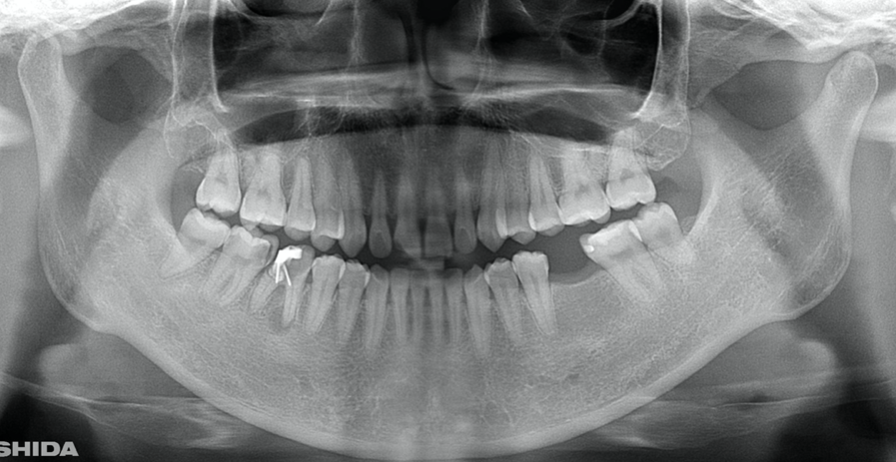

A 27-year-old female patient came to us with discomfort in the right lower jaw (Figure 1). Her primary symptoms were pain in the lower right tooth when biting and discomfort associated with not being able to chew well with the lower left single denture. The patient was married and had one young child, and previously received dental treatment in China, then had returned to Japan for childbirth and early childcare. The patient was a nonsmoker with moderate plaque control and medical history taking revealed no problems. In clinical and radiographic examinations, a root fracture was observed on tooth #46, which had been endodontic ally treated and restored with a full-cast metal crown. Periodontal probing revealed a pocket depth of 8 mm on the buccal center side of the tooth. No pain was detected with percussion and mobility of the tooth was normal. (Figure 1, Figure 2, Figure 3).

Figure 1.Clinical case of right auto transplantation. Panoramic view at initial examination.Tooth #46 was shown to be half decayed and a cystic lesion was found in the mesial root apex. Tooth #36 was lost, while #48 and #38 were present. There was a total of 29 teeth in the oral cavity.